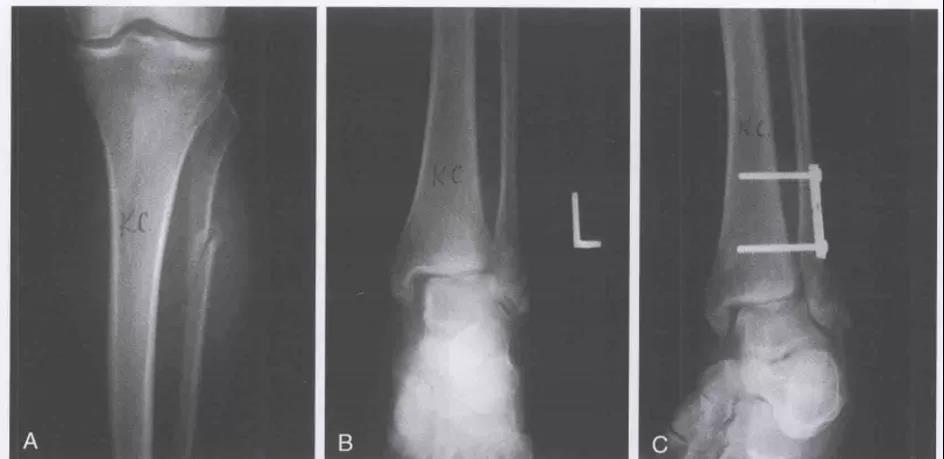

术前DR

术前CT

切口选择

复位顺序